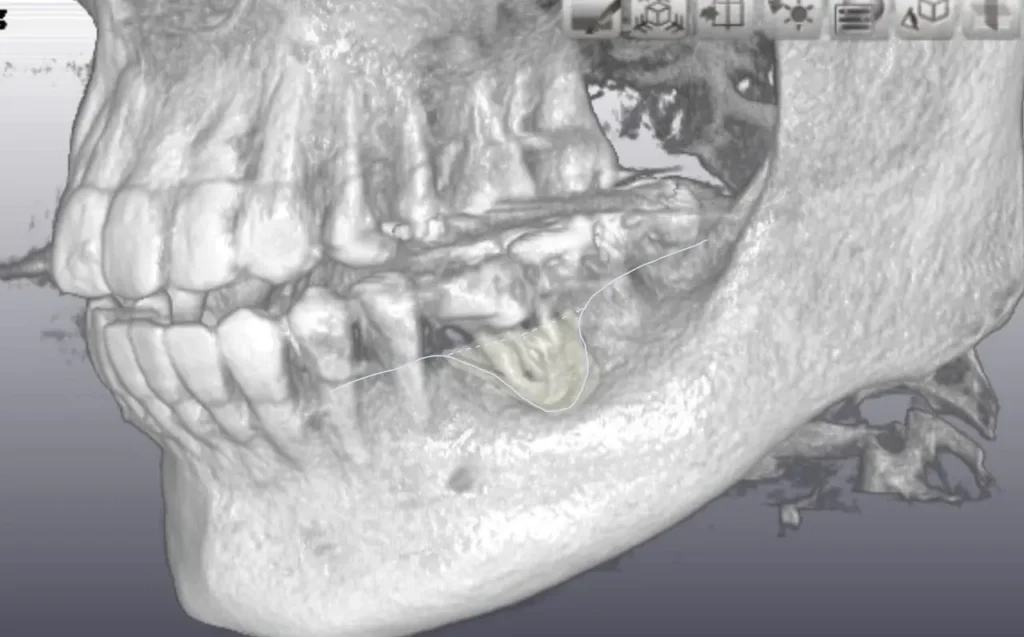

移植直後は支える骨が少ないです。

骨もしっかり増生してよく機能しています。